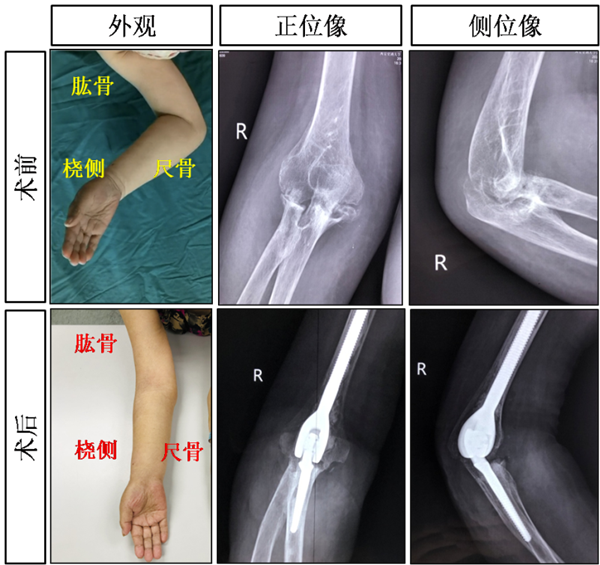

右肘关节全部置换术前/术后改变

肘关节解剖结构破坏严重,炎症导致的病变位于肘窝附近,重要血管、神经密布,术中准确切除破坏骨质,重建肘关节结构,恢复肘关节功能困难重重。面对挑战,骨一科迎难而上,术前充分准备,与工程师多次协商,个性化定制国产铰链式人工肱尺关节假体。在主任党晓谦教授的指导下,2021年05月13日由时志斌主任医师主刀,在倪建龙主治医师、冯萌住院医师、高旭规培医师的密切配合下,于全麻下施行右侧肘关节全部置换术(total elbow arthroplasty,TEA)。术中探查发现右侧肘关节滑膜翳侵入肱骨髁及桡骨近端,上尺桡关节不稳定,经过1个半小时的奋战,终于完整切除滑膜及破坏的骨质,并重建肱尺关节。

类风湿性关节炎(rheumatoid arthritis, RA)是一种病因尚未明了的自身免疫炎性疾病,俗称类风湿,好发于手、腕及足等小关节,以慢性、对称性、多滑膜关节炎和关节外病变为主要临床表现。RA早期常有关节僵硬,肿痛和功能障碍,晚期关节可出现不同程度的僵硬畸形,并伴有骨质疏松和骨骼肌的萎缩,如不进行正规治疗,极易致残。术后病理结果回报:“右肘关节”滑膜炎症改变,伴纤维组织增生及软骨化生。患者规律口服艾拉莫德控制活动性类风湿性关节炎3周,辅助系统的功能训练及专业的康复指导,患者右前臂肿胀明显消退、肘关节活动度极大改善。患者及家属极其满意,出院回家。全肘关节置换术是治疗终末期肘关节炎的有效外科手段,但与髋、膝关节置换术相比,其假体存活率仍较低而术后并发症发生率更高。本例患者从发现、诊断、手术到患者随访总共约3月时间。术后未发生肘关节假体周围感染、假体周围骨折、假体组件失效和无菌性松动,体现出我院骨一科时志斌教授带领的运动医学组在骨骼肌肉运动系统疑难疾病的诊治中具有扎实的功底和较高的水平,并具有强大的关节重建综合实力及指导肘关节置换患者的康复经验。

肘关节全部置换术示意图及术后康复效果图